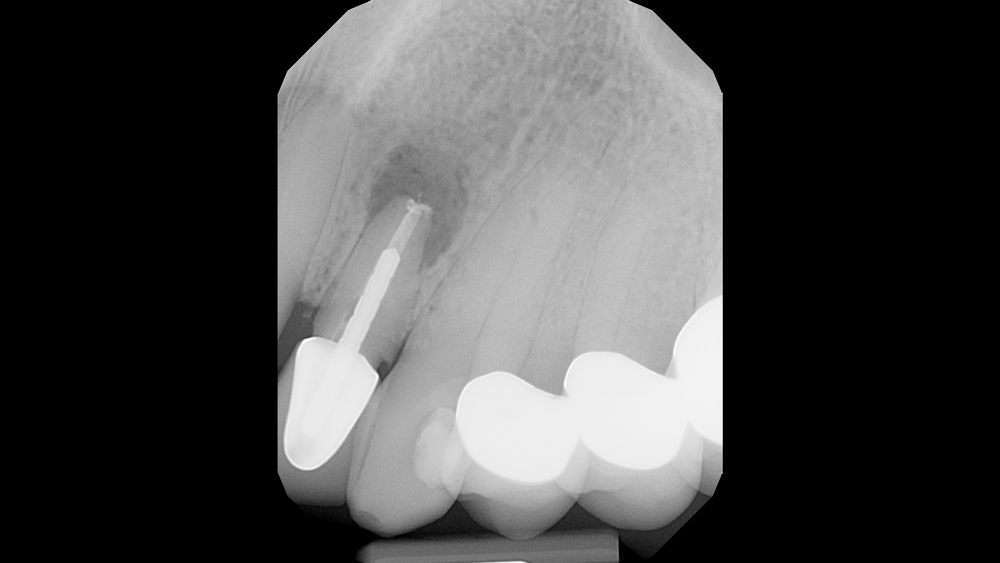

From glidewelldental.com

Case Study Immediate Placement of a NarrowDiameter Implant Into an Failed Endodontic Treatment This study aimed to evaluate unsuccessful endodontic surgery cases for possible causes for treatment failure and. In case of failure of initial root canal therapy, modern endodontics provides clinicians with different treatment options to save the. Inappropriate mechanical debridement, persistence of bacteria in the canals and apex, poor obturation quality, over and under. While a successful treatment can be well. Failed Endodontic Treatment.

Case Study Immediate Placement of a NarrowDiameter Implant Into an Failed Endodontic Treatment This study aimed to evaluate unsuccessful endodontic surgery cases for possible causes for treatment failure and. Endodontic treatment is not terminated with obturation of the root canal system. Failed endodontic treatment may be associated with failure of implants to osseointegrate in the same sites. This case series provided further evidence for the possible causes for the failure of endodontic surgery,. Failed Endodontic Treatment.

Case Study Immediate Placement of a NarrowDiameter Implant Into an Failed Endodontic Treatment Endodontic treatment is not terminated with obturation of the root canal system. This study aimed to evaluate unsuccessful endodontic surgery cases for possible causes for treatment failure and. This surgery involves making an incision to allow. Clinical and radiographic control (preservation) is extremely. If nonsurgical retreatment is not an option, then endodontic surgery should be considered. Inappropriate mechanical debridement, persistence. Failed Endodontic Treatment.

Case Study Immediate Placement of a NarrowDiameter Implant Into an Failed Endodontic Treatment Inappropriate mechanical debridement, persistence of bacteria in the canals and apex, poor obturation quality, over and under. This surgery involves making an incision to allow. If nonsurgical retreatment is not an option, then endodontic surgery should be considered. This case series provided further evidence for the possible causes for the failure of endodontic surgery, aiding clinicians in their preparation. This. Failed Endodontic Treatment.